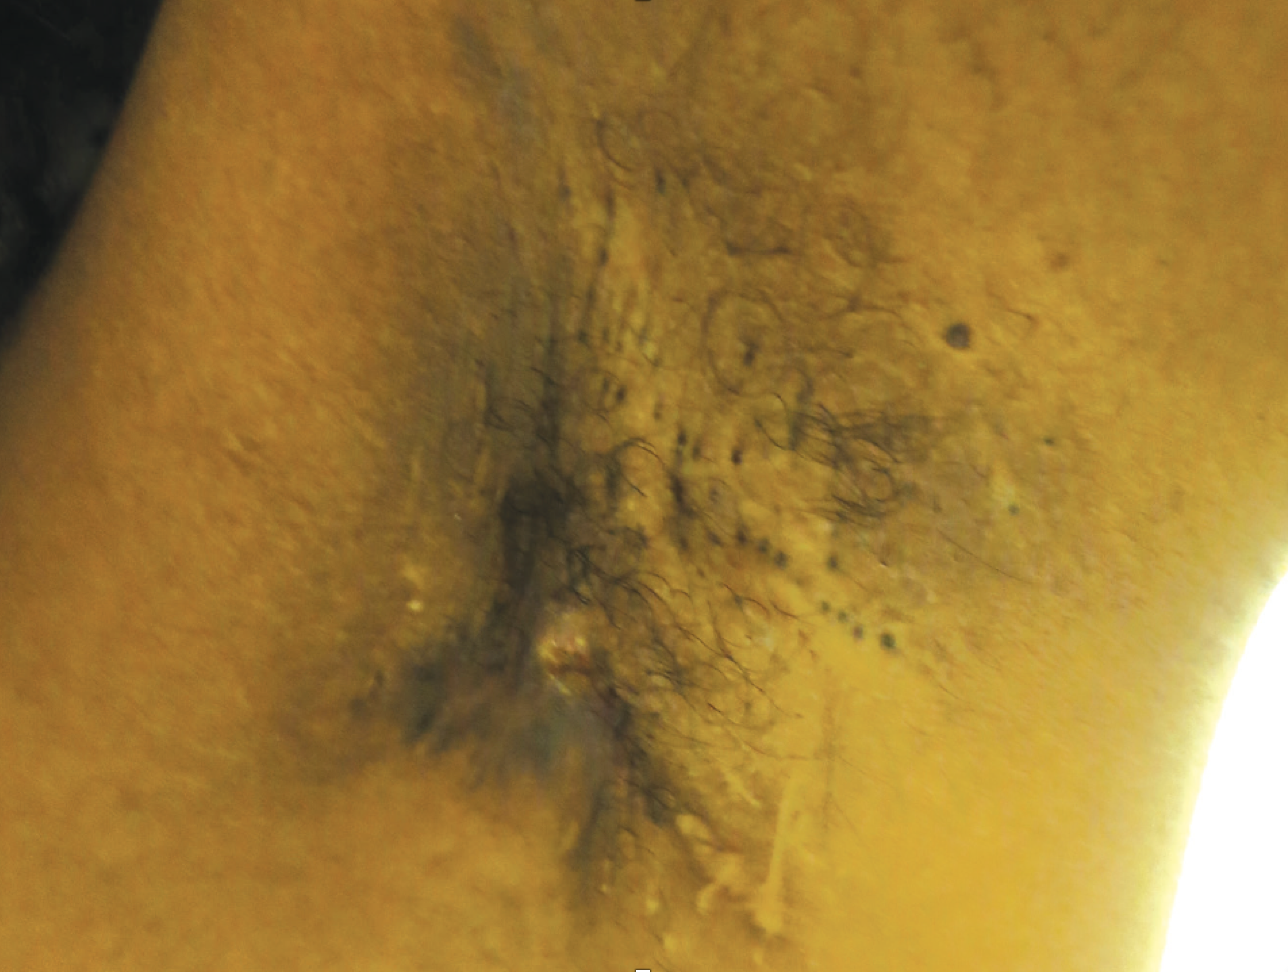

Left Axillary Pain and Malaise in a 29-Year-Old Woman

A 29-year-old African American female with a history of axillary hidradenitis suppurativa (HS) on oral clindamycin and doxycycline suppressive therapy presented to a forward deployed clinic in an austere, hot, and humid environment for increasing pain in her left axilla. She was diagnosed with a left axillary abscess and treated with incision and drainage. Five days later, she returned to the clinic with worsening left axillary pain and general malaise. Physical examination revealed temperature of 103.2˚ F, heart rate of 144 beats/min, blood pressure of 118/78 mmHg, and respiratory rate of 14 breaths/min. Laboratory testing revealed a white blood cell count of 22.4 x103 cells/µL with 95.7% granulocytes. Complete physical exam and review of systems was negative for any other source of infection. Diagnosed with sepsis due to left axillary soft tissue infection, she was admitted to the intensive care unit and treated with intravenous fluid resuscitation and intravenous clindamycin. Repeat incision and drainage of the left axillary abscess produced purulent material, and the wound was subsequently packed.

HS is a chronic inflammatory condition characterized by painful, deep-seated nodules, abscesses, and sinus tracts. Clinical diagnosis is made upon the presence of typical lesions in intertriginous regions with apocrine glands (i.e., axillary, inframammary, inguinal, gluteal, and perineal). Though previously thought to be caused by dysfunctional apocrine glands, HS is now included in the follicular occlusion tetrad, which includes acne conglobata, dissecting cellulitis of the scalp, and pilonidal cysts. Follicular infundibular occlusion is likely the inciting event, followed by follicular rupture and local inflammatory changes.1 However, the exact pathogenesis remains uncertain.

The patient was transferred back to the United States for continued medical care. One month after discharge, Dermatology evaluation revealed scarred sinus tracts in bilateral axillae without active inflammation or infection. Her current treatment regimen consists of daily oral doxycycline, benzoyl peroxide, and silver sulfadiazine as needed on active lesions. Future treatment considerations include laser hair removal and adalimumab.